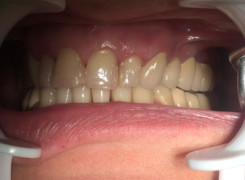

Pan Ryszard trafił do Naszego Gabinetu z jasno sprecyzowanym oczekiwaniem. Miał 84 lata i chciał odzyskać możliwość swobodnego spożywania posiłków oraz poprawienia sobie komfortu życia a także prosił aby przywrócić mu piękny uśmiech jakim cieszył się przed laty. Już na początku pierwszej rozmowy zastrzegł, że interesuje go wyłączenie rozwiązanie uzupełnieniem protetycznym stałym. Nie miał zamiaru użytkować żadnych protez ruchomych. Mając na uwadze powyższe wykonaliśmy Panu Ryszardowi zdjęcie pantomograficzne oraz badanie tomograficzne szczęki i żuchwy na postawie których zapanowywaliśmy Pacjentowi optymalne rozwiązanie – stałe uzupełnienie protetyczne w postaci 28 koron cyrkonowych zamontowanych do dwóch belek cyrkonowych które będą przymocowane do 16 implantów w konfiguracji 8 wszczepów w szczęcie 8 w żuchwie. Po omówieniu powyższego planu przystąpiliśmy do Wspólnej pracy której efekty w poszczególnych etapach prezentujemy poniżej.